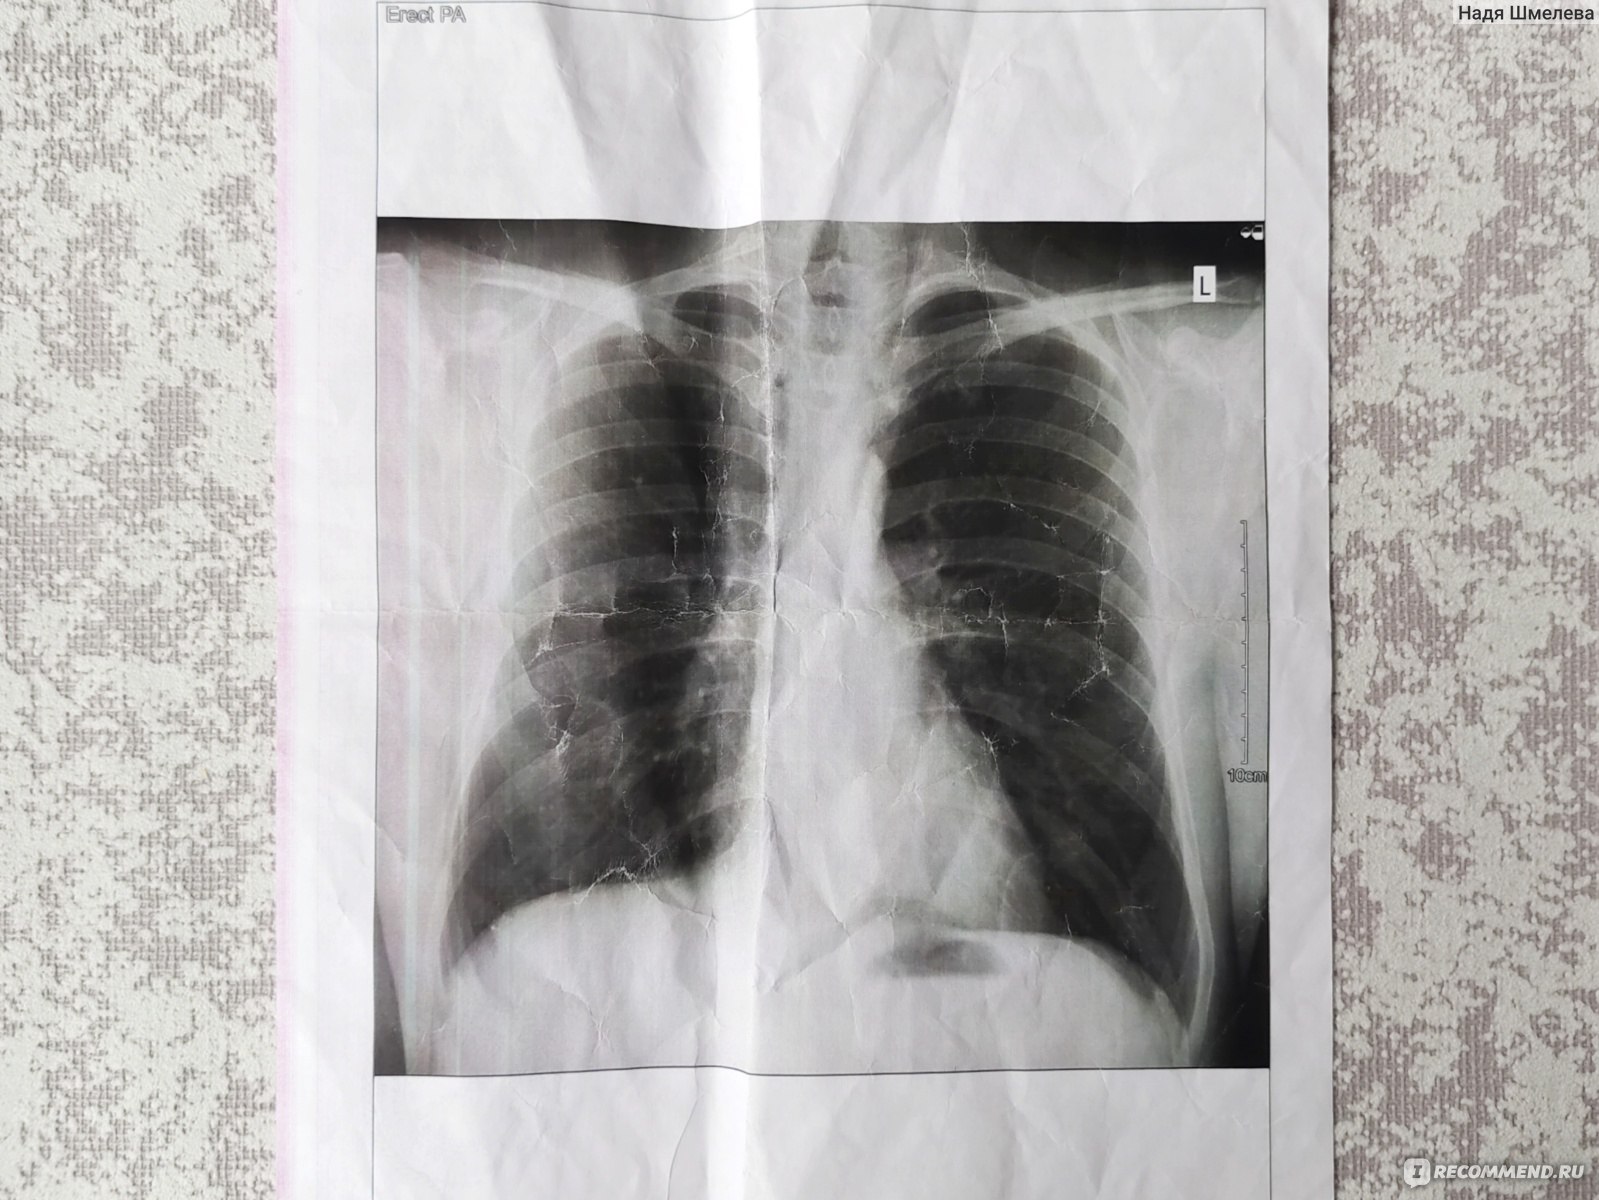

Изучение дозы излучения при рентгеновских исследованиях: визуализация